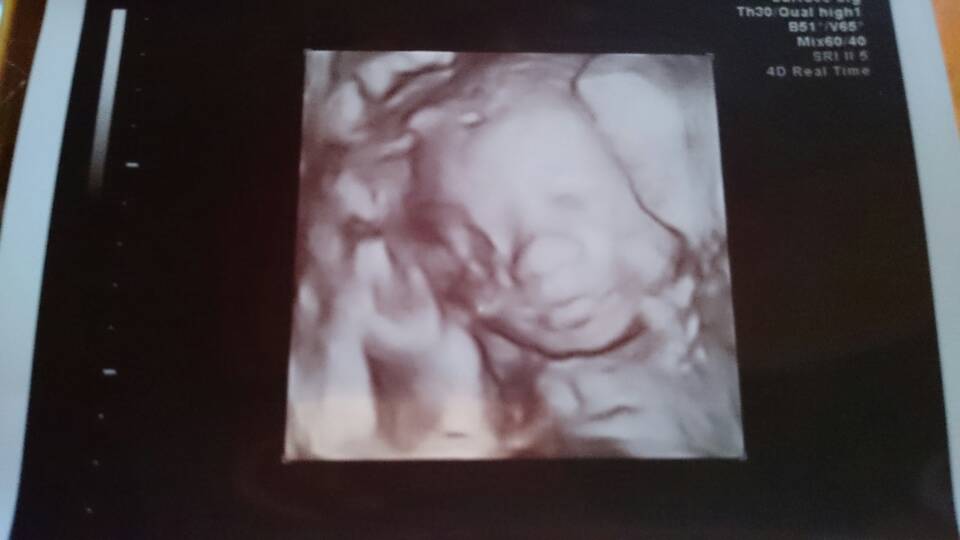

U nas też wszysyko dobrze [emoji2] Lili zostaje Lilianką na 200% [emoji7] gin robił zbliżenie na siśkę i wyraźnie pokazywał mi ze tam już siusiak nie ma szans się pojawić [emoji23] maleńka waży cale 700g i leży poskladana jak scyzoryk z rękami i nogami na głowie [emoji16] i to wyjaśnia dlaczego ruchy czuję doslownie wszędzie [emoji6] mam się powoli przymierzyć do wypicia glukozy przed następną wizytą. Z gorszych wieści z wymazu bakteriologicznego pochwy wyszła mi e. coli która nie daje żadnych objawów. Także od dziś aplikuje globulki przez tydzień.

Oto moja kolejna miłość do grobowej deski!! [emoji7]

1475521840006.jpg

1475521847297.jpg

1475521853748.jpg

• 1475521840006.jpg

55 KB · Wyświetleń: 578

• 1475521847297.jpg

47,8 KB · Wyświetleń: 578

• 1475521853748.jpg

24,7 KB · Wyświetleń: 557